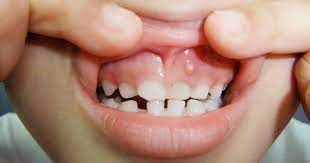

Gum Boils What S That Dr Alan Macdonald Dentist

Gum Boils What S That Dr Alan Macdonald Dentist from dralanmacdonald.com